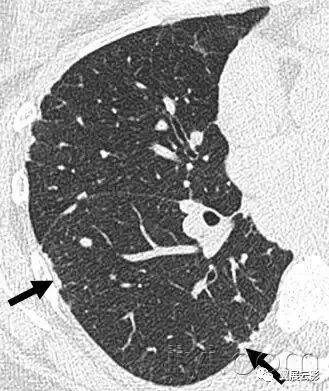

十八、小叶中心性:

解剖:小叶中心性用于描述次级肺小叶的支气管血管束中心区域。病理学上也用这一术语描述终末小支气管远端,位于呼吸性细支气管和肺泡管中心的病变。

CT:正常次级肺小叶中心的点状或者线状的密度增高影,胸膜下25px范围内最明显,代表小叶内的动脉,直径约1mm。

小叶中心性异常包括(1)结节(2)树芽征,提示小气道病变(3)由于临近间质的增厚或者浸润导致小叶中心结果更加清晰(4)小叶中心性肺气肿导致的异常低密度。

附图为小叶中心性肺气肿